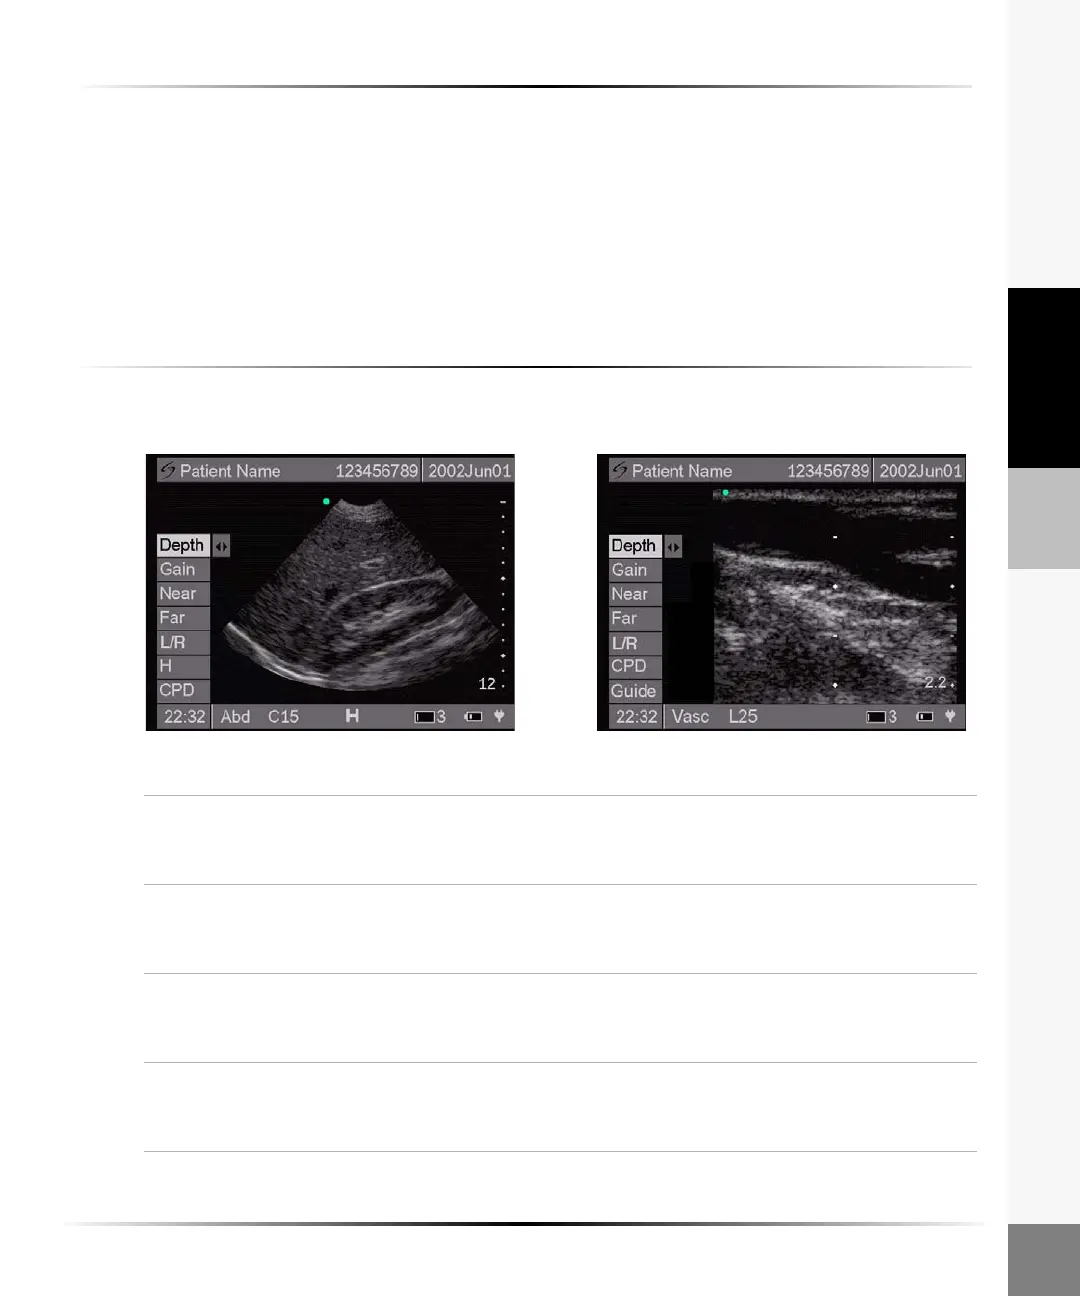

For C15 For L25

2D Image

To optimize the 2D image:

Depth 1 Highlight Depth from the on-screen menu.

2 Arrow right to increase depth and left to decrease depth.

Note: The number in the lower right corner indicates the depth in centimeters.

Gain 1 Highlight Gain from the on-screen menu.

2 Arrow right to increase gain and left to decrease gain.

Note: Gain adjusts the overall gain applied to the entire image.

Near 1 Highlight Near from the on-screen menu.

Note: Near adjusts the gain applied to the near field of the image.

Far 1 Highlight Far from the on-screen menu.

Note: Far adjusts the gain applied to the far field of the image.